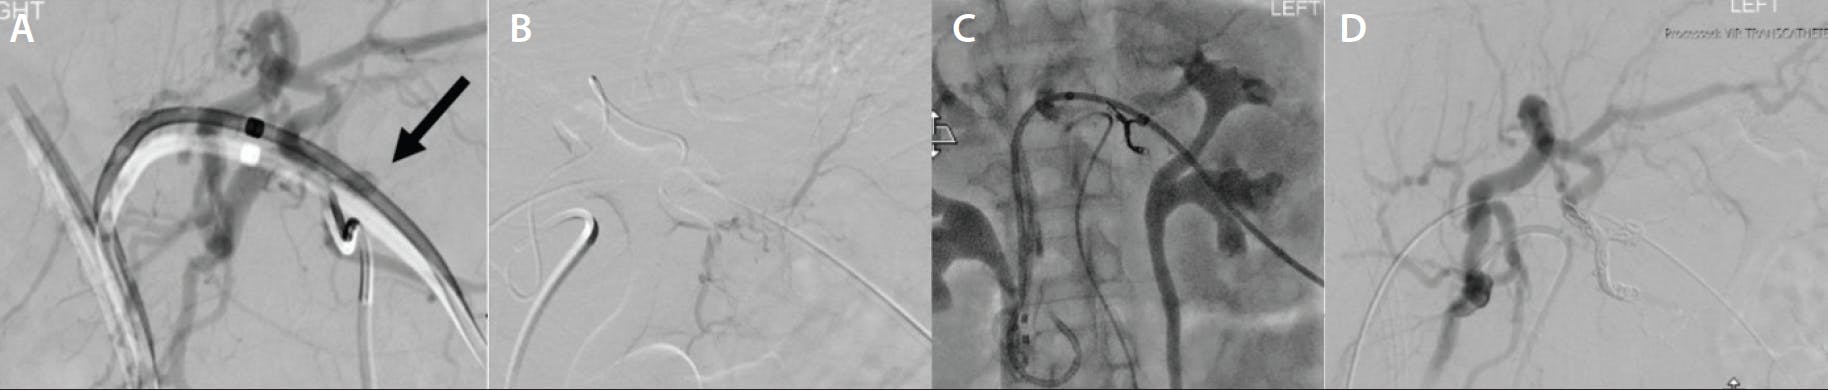

A male patient in his early 60s who was on hemodialysis for end-stage renal disease and had diabetes and severe atherosclerotic disease presented with benign prostatic hyperplasia with lower urinary tract symptoms and urinary incontinence with long-term Foley catheter dependence. After a multidisciplinary discussion with urology, the patient was referred to interventional radiology for prostatic artery embolization. Pelvic angiography demonstrated extremely tortuous iliac vessels with multifocal stenoses in the pelvic vasculature (Figure 1A). Superselective angiography of the left internal iliac artery showed pin-hole severe stenosis of the prostatic artery origin (Figure 1B and 1C). Multiple 0.014- and 0.016-inch microwires were utilized with differing tip shapes. Ultimately, the 0.016-inch Glidewire GT-R microwire was used, which crossed a tight stenosis relatively quickly despite seeming initially impossible to traverse. Later in the case, the durable shapeable tip and reshapeable nature of the wire came in handy when crossing additional stenoses on the contralateral side.

Figure 1. Pelvic angiogram showing extremely tortuous iliac vessels with multifocal stenoses in the pelvic vasculature (A). Superselective angiography of the left internal iliac artery shows pin-hole severe stenosis of the prostatic artery origin (B, C).